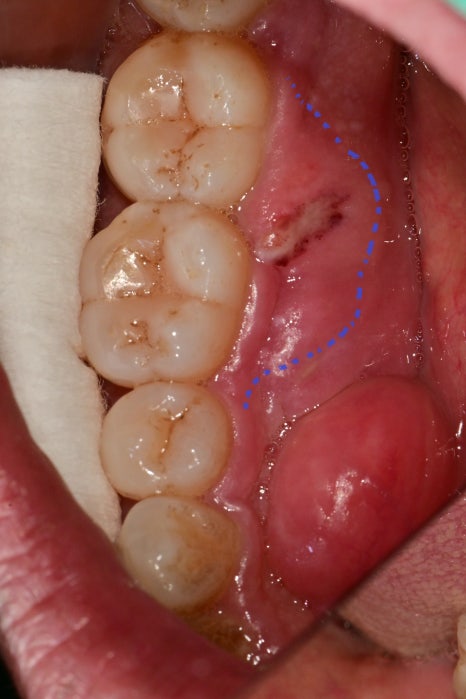

그 이후에 다음번에 오실 때는 어금니 쪽 잇몸에 뭐가 생겼다가 없어진다는 주소로 찾아오셨습니다.

혀쪽의 잇몸이 부어있고 헐어있었습니다.

엑스레이를 찍어보니 특이하게도 바깥쪽이 아닌 안쪽 뼈가 파란색 선까지 파괴가 되어있었습니다.

앞서 말씀드렸듯이 치아와 잇몸 사이의 공간은 3mm 내외가 되어야 정상인데

이 경우는 10mm가 넘어가는 이미 진행이 많이 된 치주염이였습니다.

이런 케이스에서는 안쪽에 마취를 먼저 시행하고,

안쪽에 치석, 플라그, 음식물 잔사들을 긁어내고

안쪽에 항생제를 넣어 잇몸의 부종을 먼저 가라앉히는 것이 우선입니다.